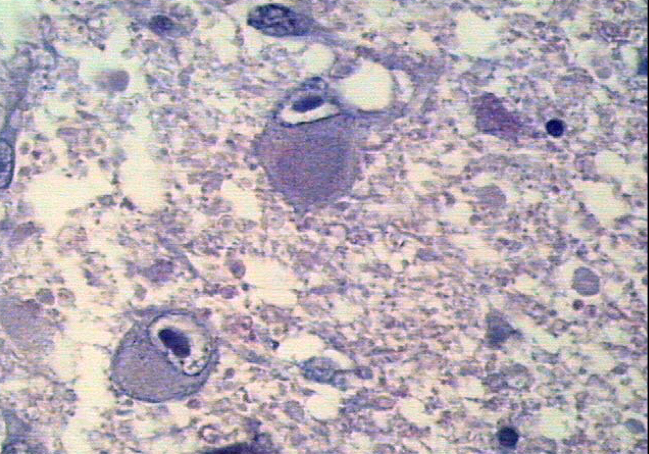

What virus is this?

CMV - can see ‘owl eyes’ which are inclusions of the virus replicating